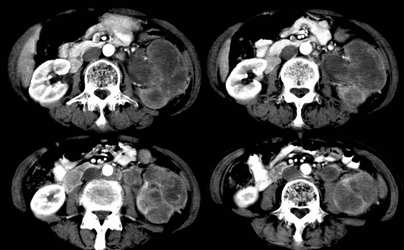

病患,女,69岁,左侧腰部不适,偶感疼痛2个月余,无化验室检查,行彩超发现左侧肾区实质性肿物,后行ct检查,结果同上。

左肾不规则软组织肿块,内见低密度坏死区,与正常肾实质分界不清,左肾明显增大,增强呈不规则条索状强化,肾盂及左输尿管上段扩张。肾周脂肪层受侵、模糊。印象:典型左肾癌。

平扫,表现为肾实质肿块,呈分叶状,肿块密度不均,内有不规则低密度区(陈旧性出血?坏死?)有的似呈囊性,增强明显不均一强化,与肾实质相比呈相对低密度的不均一肿块,肾周脂肪间隙可见,肾前筋膜未见增后,肾血管及腹主动脉旁未见肿大淋巴结影

三期抓的不错,典型的肾癌,且已累及肾盂及左输尿管上段